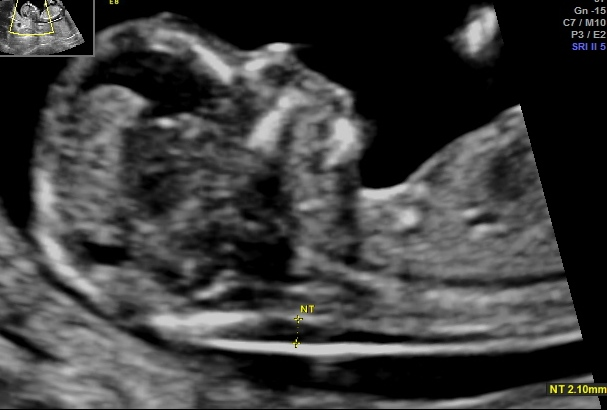

Naszym atutem jest również profesjonalny sprzęt ultrasonograficzny oraz nowoczesne wyposażenie gabinetów, którymi dysponujemy na co dzień.

Arkadiusz Krzyżanowski - na codzień pracuję w Katedrze i Klinice Położnictwa i Patologii Ciąży (Szpital SPSK1 - Staszica 16) Uniwersytetu Medycznego w Lublinie, gdzie oprócz opieki nad pacjentami w zakresie Położnictwa, Patologii Ciąży i Perinatologii zajmuję się dydaktyką studentów Wydziału Lekarskiego naszego Uniwersytetu jak i pracą badawczą. Moje najważniejsze osiągnięcia to: Doktorat z zagadnień porodu przedwczesnego, Habilitacja z zakresu pogłebionej diagnostyki prenatalnej oraz zaawansowanych badań nad komórkami macierzystymi. Jestem autorem i współautorem ponad 180 doniesień i publikacji, w tym 86 artykułów o charakterze naukowym jak i dydaktycznym w renomowanych czasopismach - wielu o zasięgu międzynarodowym. Moje zainteresowania wynikają z mojej pasji - chęci niesienia pomocy.

Perinatologia zwana też medycyną matczyno-płodową jest dziedziną medycyny zajmującą się opieką nad dzieckiem jeszcze w okresie płodowym. Celem tej opieki jest określenie najwłaściwszego sposobu prowadzenia ciąży czy możliwości wykonania ratujących życie zabiegów chirurgicznych w przypadku wykrycia w badaniach prenatalnych wady u płodu.

Dostępność badań, nowoczesny sprzęt diagnostyczny oraz specjalistyczna wiedza umożliwiają wychwycenie pewnych wad wrodzonych. Należy podkreślić, że niestety nie zawsze i nie wszystkich. Czasami możliwe jest leczenie jeszcze przed narodzinami.